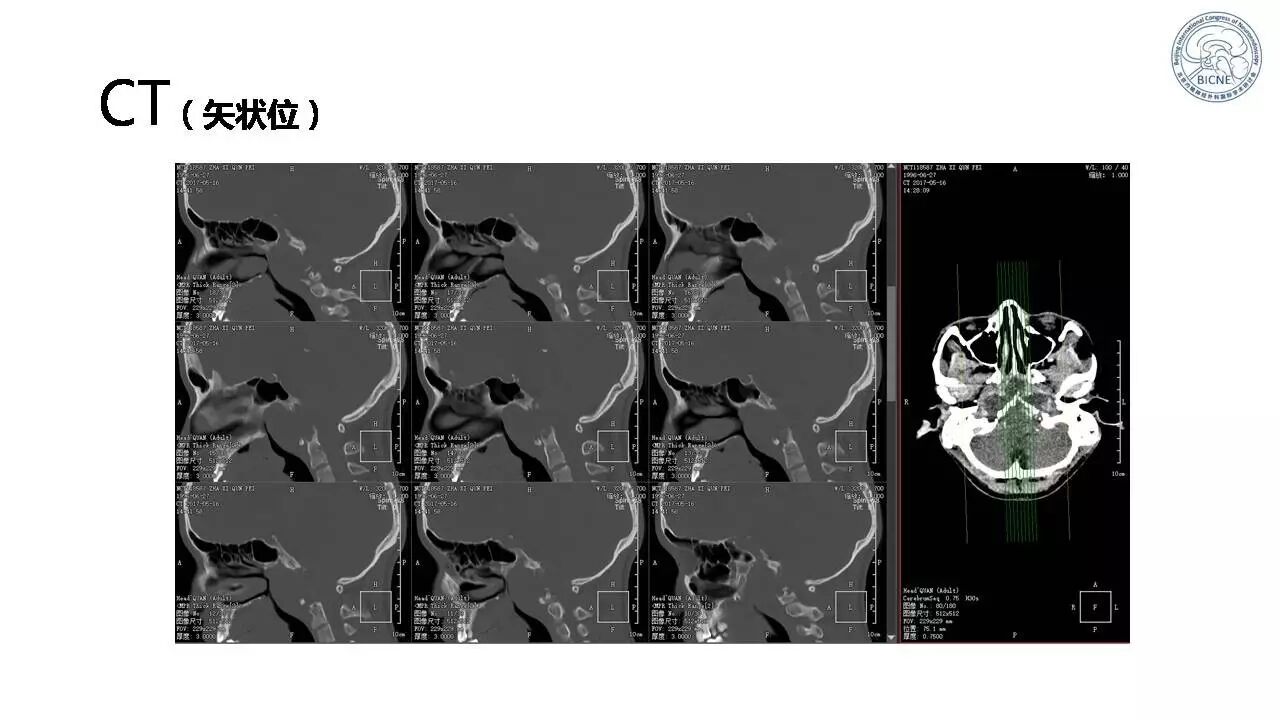

(四)张亚卓教授:复发脊索瘤经鼻内镜治疗